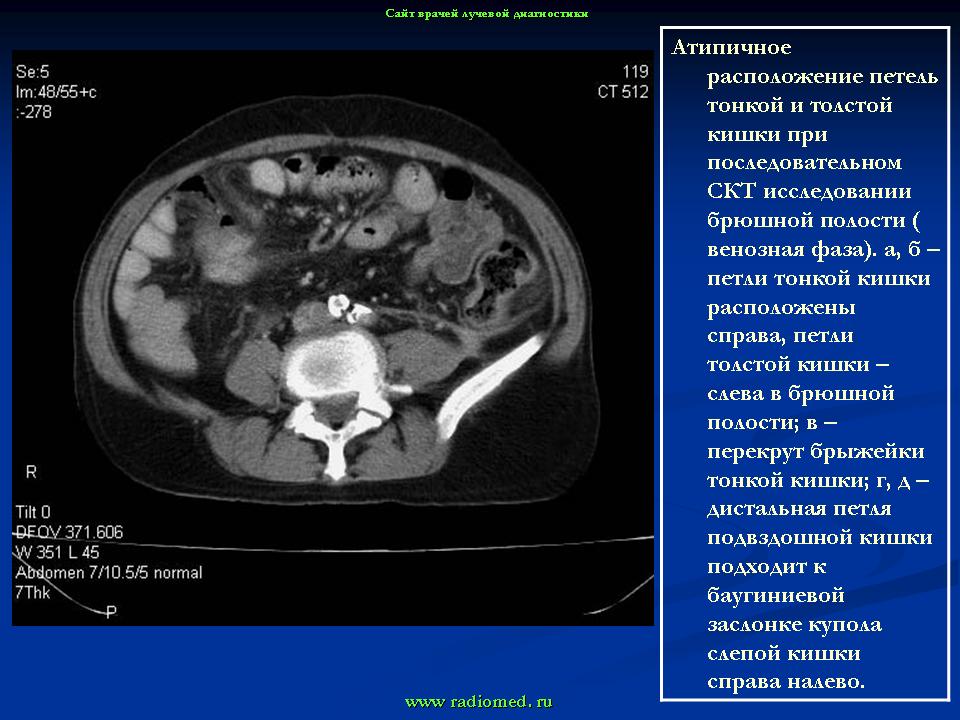

Варианты и аномалии развития толстой кишки.